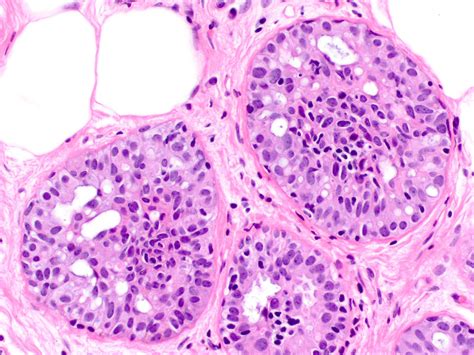

To understand Atypical Ductal Hyperplasia, it helps to look at how breast tissue changes. In a healthy breast, cells line the ducts (the tubes that carry milk). Sometimes, these cells begin to grow in an uncontrolled or disorganized manner. This process is called hyperplasia.

When those cells not only multiply but also begin to look and behave differently than normal cells—yet are not considered cancer—it is classified as “atypical.” Therefore, ADH represents a state of overgrowth where the cells lining the breast ducts have acquired some features of cancer but remain confined within the ductal structure. It is essentially a marker that indicates your breast cells are prone to genetic changes that could lead to breast cancer in the future.